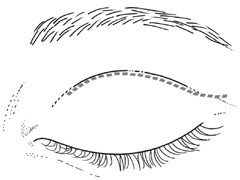

close postoperative monitoring of vision. EYELID CREASE LATERAL ORBITOTOMY This approach affords excellent exposure of the lateral orbital rim through

an incision placed within the upper eyelid crease, which may extended

laterally into a temporal “laugh line” (Fig. 6). Infiltration with local anesthetic with epinephrine (1:200,000) at

least 10 minutes before performing the skin incision minimizes

bleeding. |

Fig. 6. Lateral orbitotomy through upper eyelid skin crease A. Photo demonstrating right globe ptosis present for more than 2 years. B. Axial CT scan showing a well outlined oval lesion in the lacrimal gland

fossa. C. Coronal CT showing lesion pushing globe inferiorly. D. Skin crease excision marked for lateral orbitotomy. E. Lateral orbital rim exposed. Bone cuts made above frontozygomatic suture

and at zygomatic arch. F. Lateral wall removed. Subperiosteal space exposed. Hard tumor could be

palpated in area of lacrimal gland. G. Benign mixed tumor of lacrimal gland removed. H. Bone sutured into place. I. Skin crease closed. |